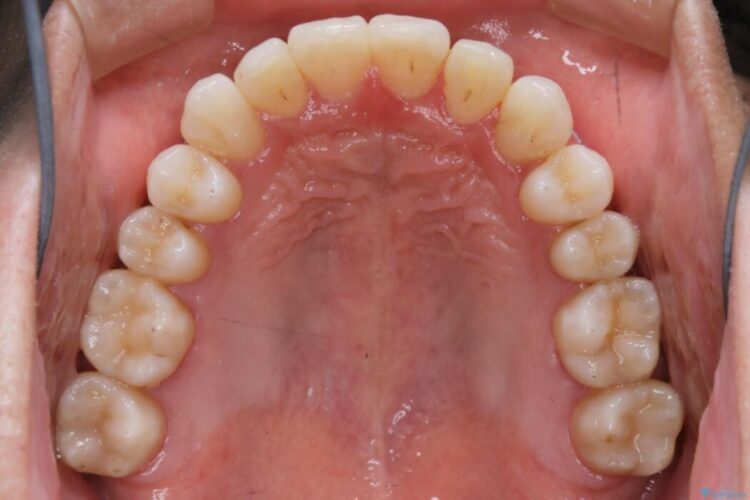

治療後について

前に出ていた前歯や目立つ八重歯(3番目の歯)もきれいに並び、奥歯の虫歯治療も並行して行ったため、機能面でも見た目的にも良くなり満足していただきました。